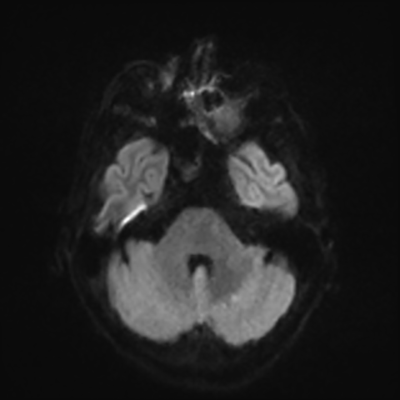

MRI brain (DWI)

You can clearly see diffuse cortical and basal ganglia diffusion restriction, and that of his deep cerebellar nuclei as well. The right occipital lobe abnormalities are a little more prominent, but then you remember that he is known to have had a right occipital stroke weeks ago.